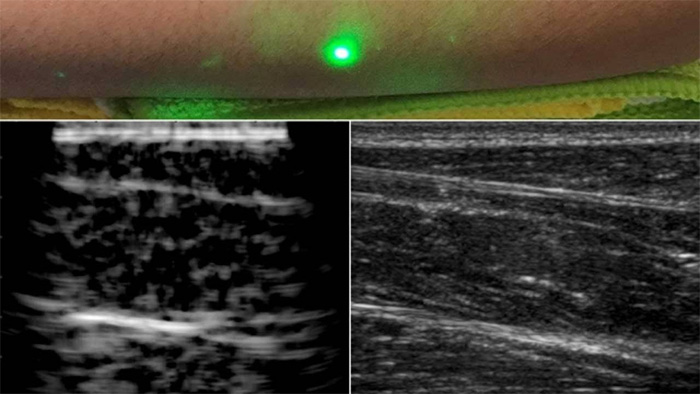

現(xiàn)在,麻省理工學(xué)院的科學(xué)家們找到了一個(gè)解決方案;他們已經(jīng)開發(fā)了一種新的激光超聲波技術(shù),一種不需要與身體接觸就能看到病人內(nèi)部的超聲波技術(shù)。該方法利用對(duì)眼睛和皮膚均安全的激光系統(tǒng)遠(yuǎn)程成像人體內(nèi)部。

為了進(jìn)行測(cè)試,科學(xué)家們對(duì)幾名志愿者的前臂進(jìn)行了成像,并觀察了皮膚以下約6厘米處的肌肉、脂肪和骨骼等常見組織特征。這些圖像與傳統(tǒng)的超聲波類似,是用遠(yuǎn)程激光聚焦在半米外的志愿者身上產(chǎn)生的。

科學(xué)家們用一臺(tái)1550納米的脈沖激光來產(chǎn)生聲波,另一臺(tái)調(diào)到相同波長(zhǎng)的連續(xù)激光來遠(yuǎn)程探測(cè)反射聲波。這第二層是一個(gè)靈敏的運(yùn)動(dòng)探測(cè)器,它測(cè)量由聲波反射到肌肉、脂肪和其他組織引起的皮膚表面振動(dòng)。反射聲波產(chǎn)生的皮膚表面運(yùn)動(dòng)引起激光頻率的變化,可以測(cè)量。通過機(jī)械地掃描全身的激光,科學(xué)家可以在不同的位置獲取數(shù)據(jù),并生成該區(qū)域的圖像。